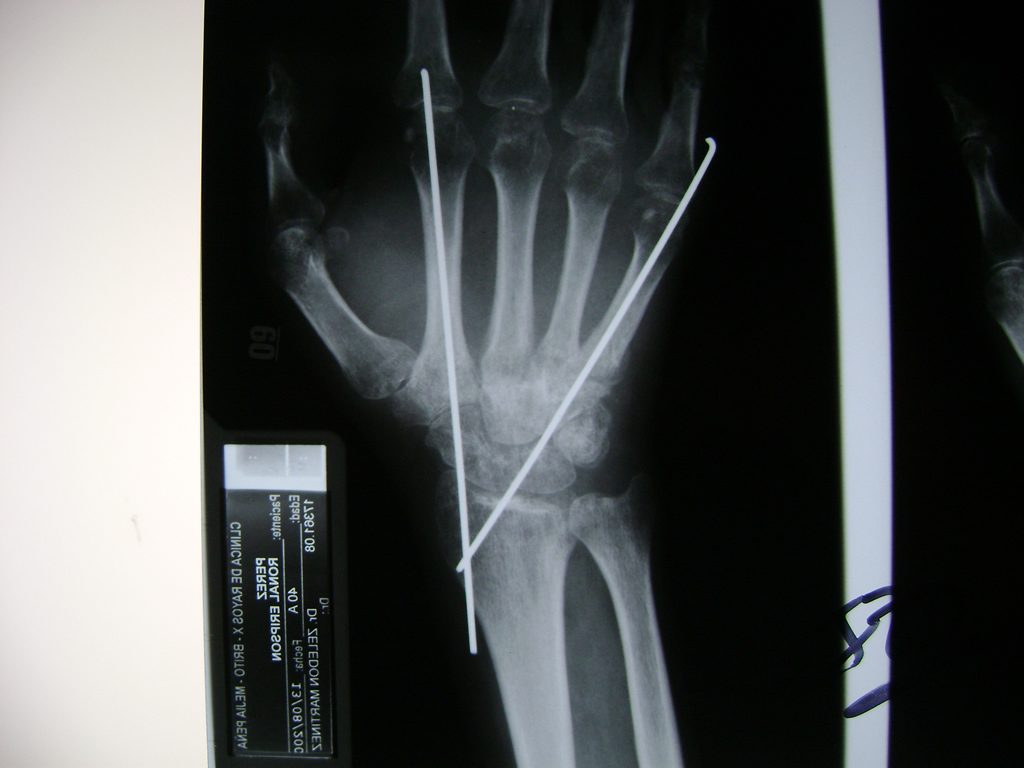

Calcaneo - Cirugías de Muñecas y Manos

Los procedimientos más comunes en cirugía de la mano son aquellos destinados a reparar traumatismos, incluyendo lesiones de tendones, nervios, vasos sanguíneos, y articulaciones; huesos fracturados; y quemaduras, cortes, y otros daños de la piel.